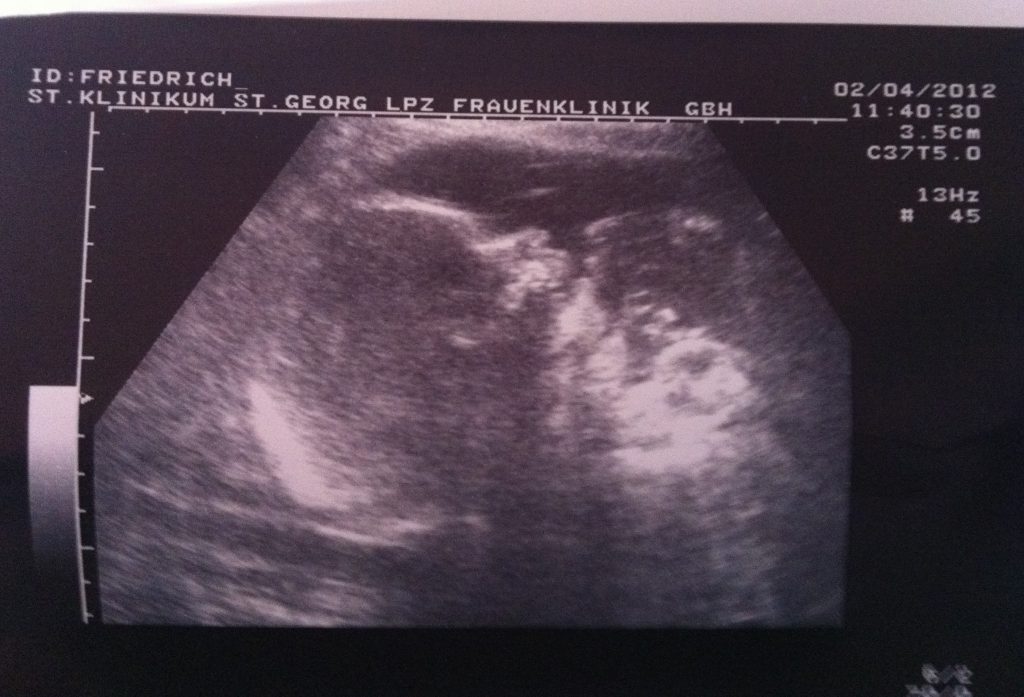

Ständiges und dauerhaftes Erbrechen, hoher Blutdruck und starke Wassereinlagerungen waren mein Begleiter. Dazu kam psychischer Stress durch Beziehungsprobleme. Lebensgefahr für Mutter und Kind. Nach mehreren Krankenhausaufenthalten und überdurchschnittlich vielen Kontrollen dann in der 31. Woche der Notfallkaiserschnitt, die Lage war lebensbedrohlich.

Am 09.04.2012 um 19.49 Uhr wird Emma-Sofie per Kaiserschnitt auf die Welt geholt. Ein Hauch von Nichts.

Gewicht: 988 g Größe: 38 cm